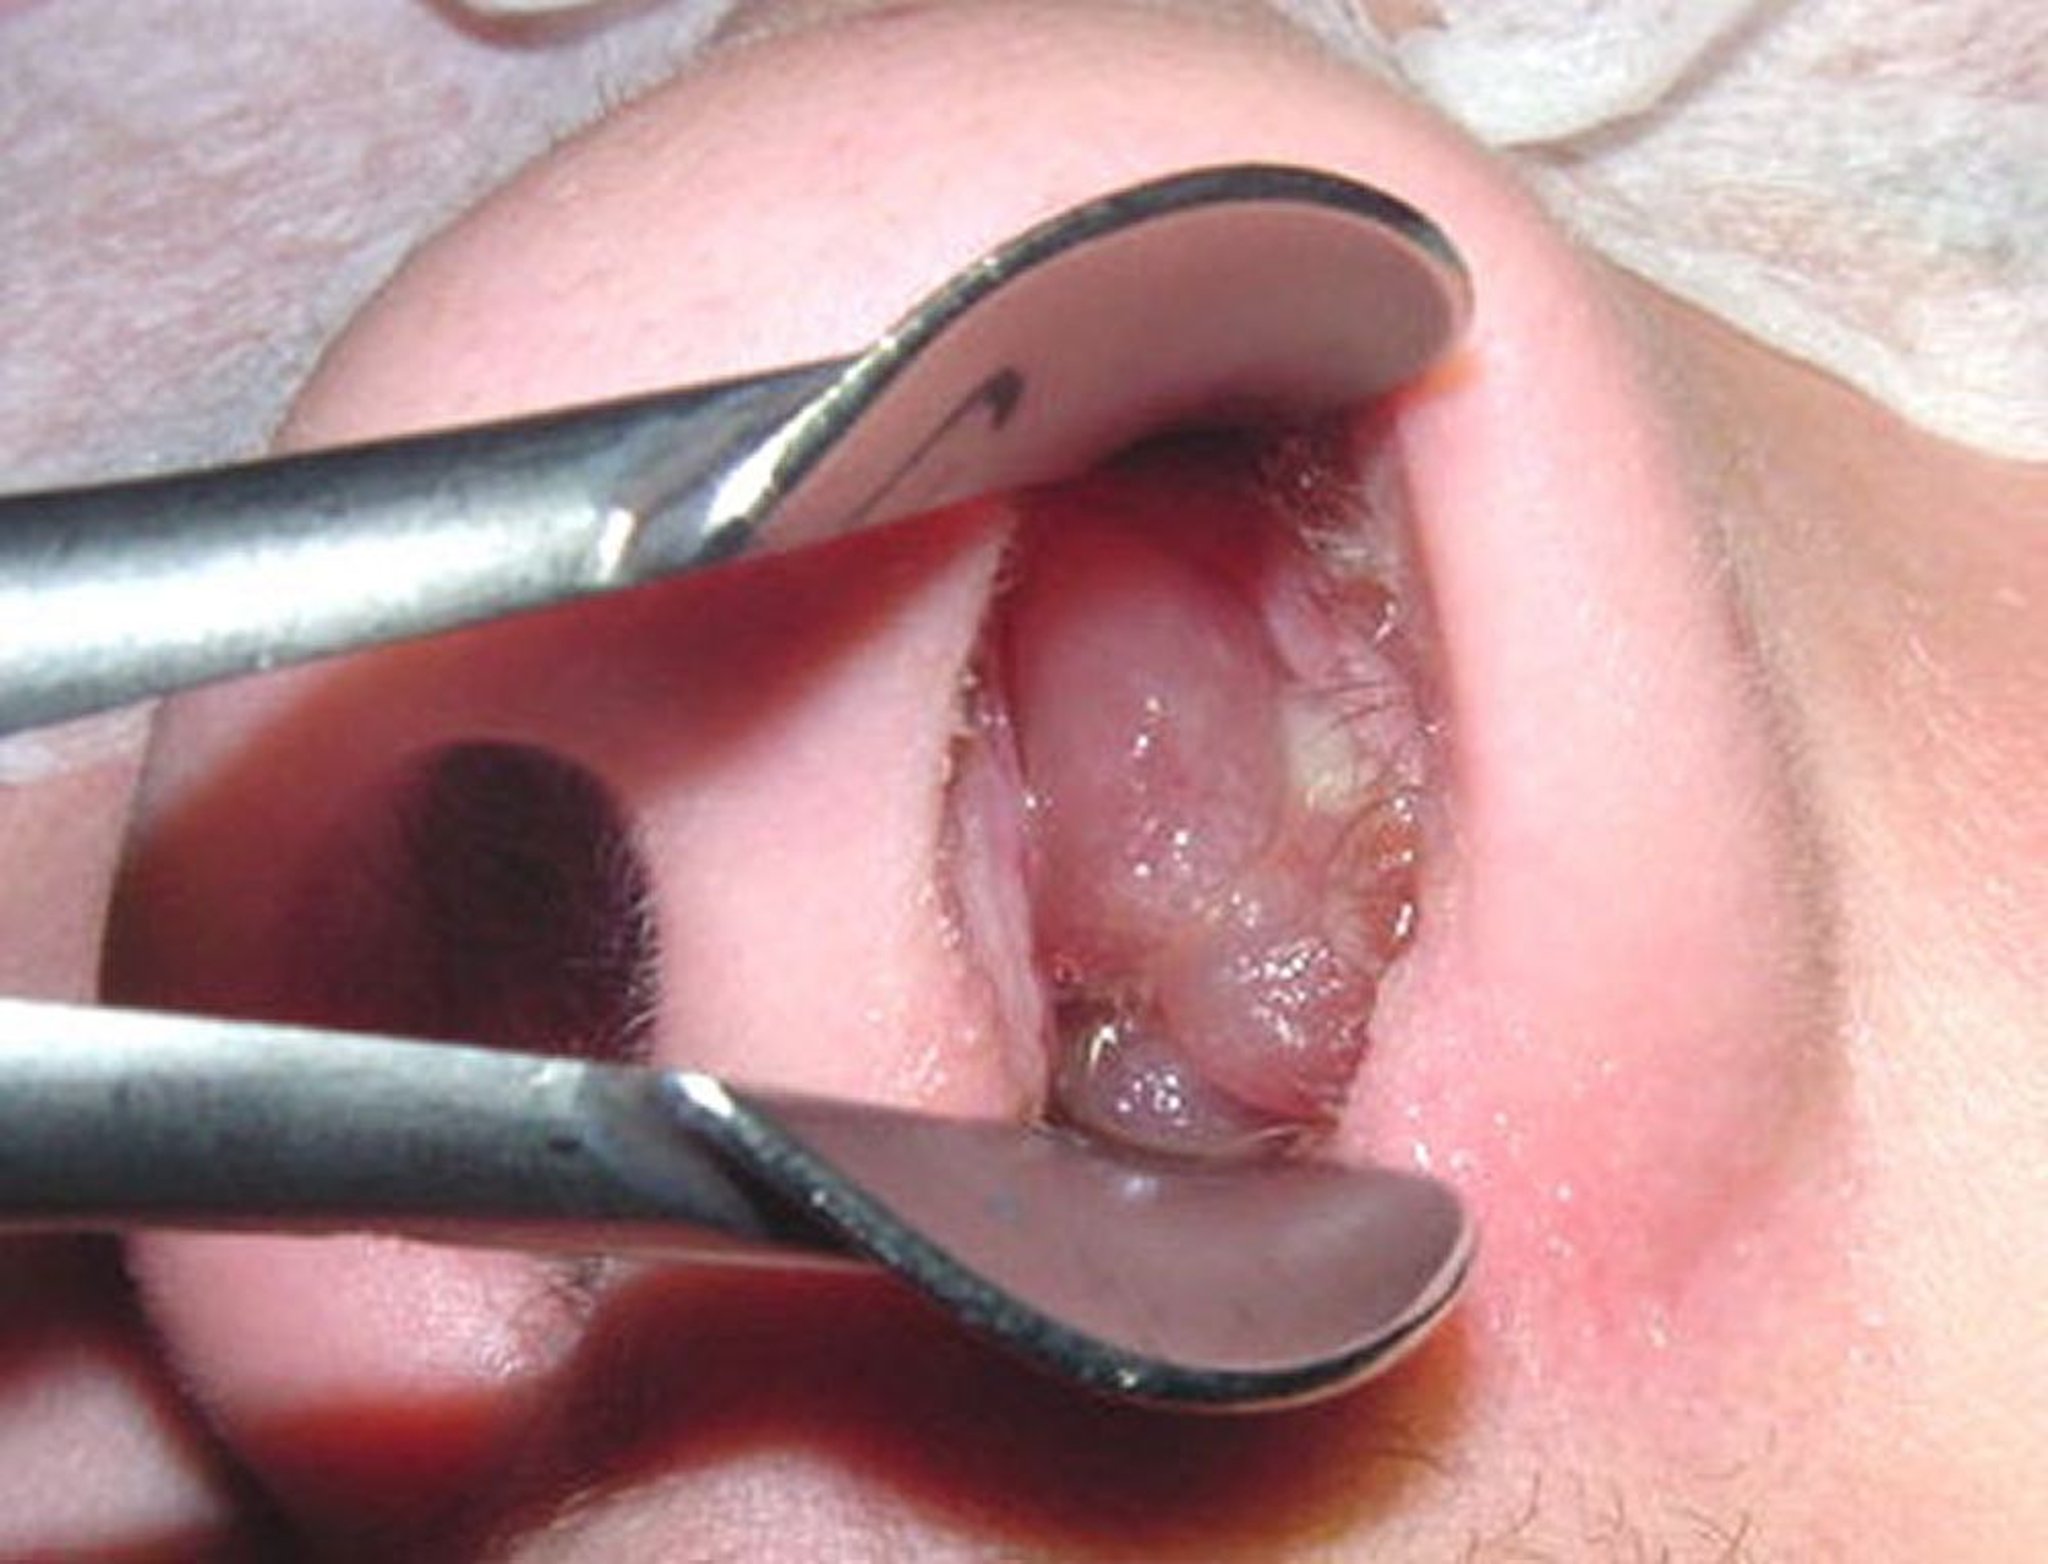

Un polipo nasale maturo può assomigliare a un acino sbucciato senza semi.

Image provided by Bechara Ghorayeb, MD.